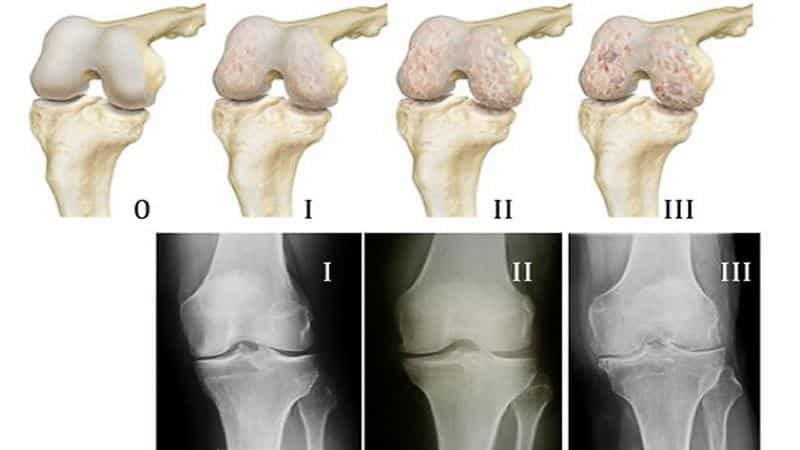

Артрозы — хронические заболевания суставов и их ближайшего окружения (околосуставных мышц, сумок и связок суставного хряща). В первой степени артроза в результате повреждения протеогликанов, отвечающих за удержание воды в хряще, хрящ «подсыхает» и теряет свою упругость и эластичность. Коллагеновые волокна начинают терять свою прочность, что приводит к шероховатости и неровности суставной поверхности, она покрывается трещинами.

При второй степени артроза кости без хрящевого амортизатора со временем начинают сплющиваться, происходит увеличение суставной площадки. По ее краям появляется перерожденная костная ткань в виде наростов — остеофитов. Происходит сморщивание патологически перерожденной капсулы сустава и синовиальной оболочки. Из-за нарушения циркуляции суставной жидкости она становится вязкой и хуже отдает хрящу питательные вещества, что ускоряет его разрушение на 50—70%.

Кости, которые лишились и смазочной суставной жидкости, и хрящевого амортизатора, при движении сустава начинают тереться друг о друга. При этом быстро наступает третья стадия артроза — почти полное исчезновение суставной щели, при которой дальнейшая работа сустава невозможна.

- Рентгенография. Является основным методом диагностики гонартроза, хотя на первой стадии может и не выявить патологию, но на второй стадии видит наличие остеофитов, участки окостенения, сужение суставной щели.